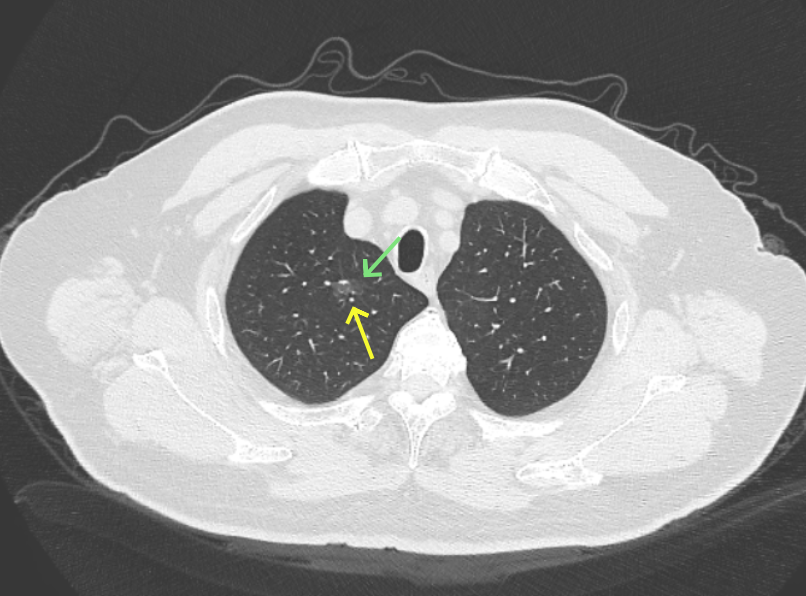

再看2026年3月最近复查时不同层面病灶A的细节影像特征:

微小血管走向病灶,磨玻璃的密度淡而较纯。

再看病灶B的2026年3月细节影像特征:

边缘位置也是较淡的磨玻璃成分。